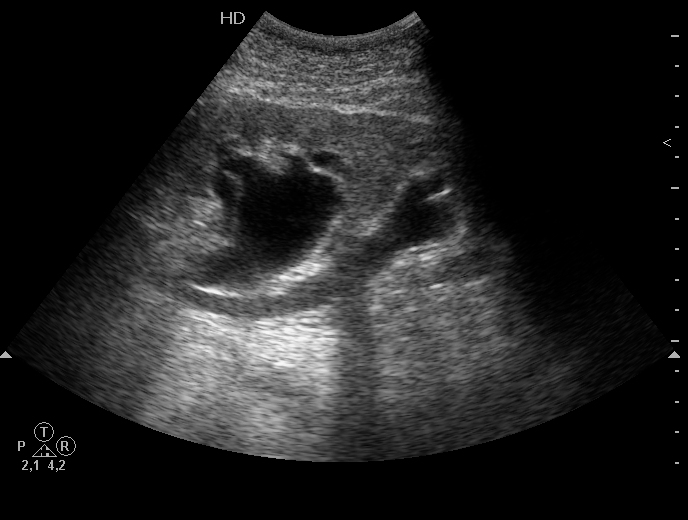

Женщина, боли в пояснице слева.

Гидронефроз, удвоение ЧЛС почки на уровне верхней трети мочеточника (ureter fissus)